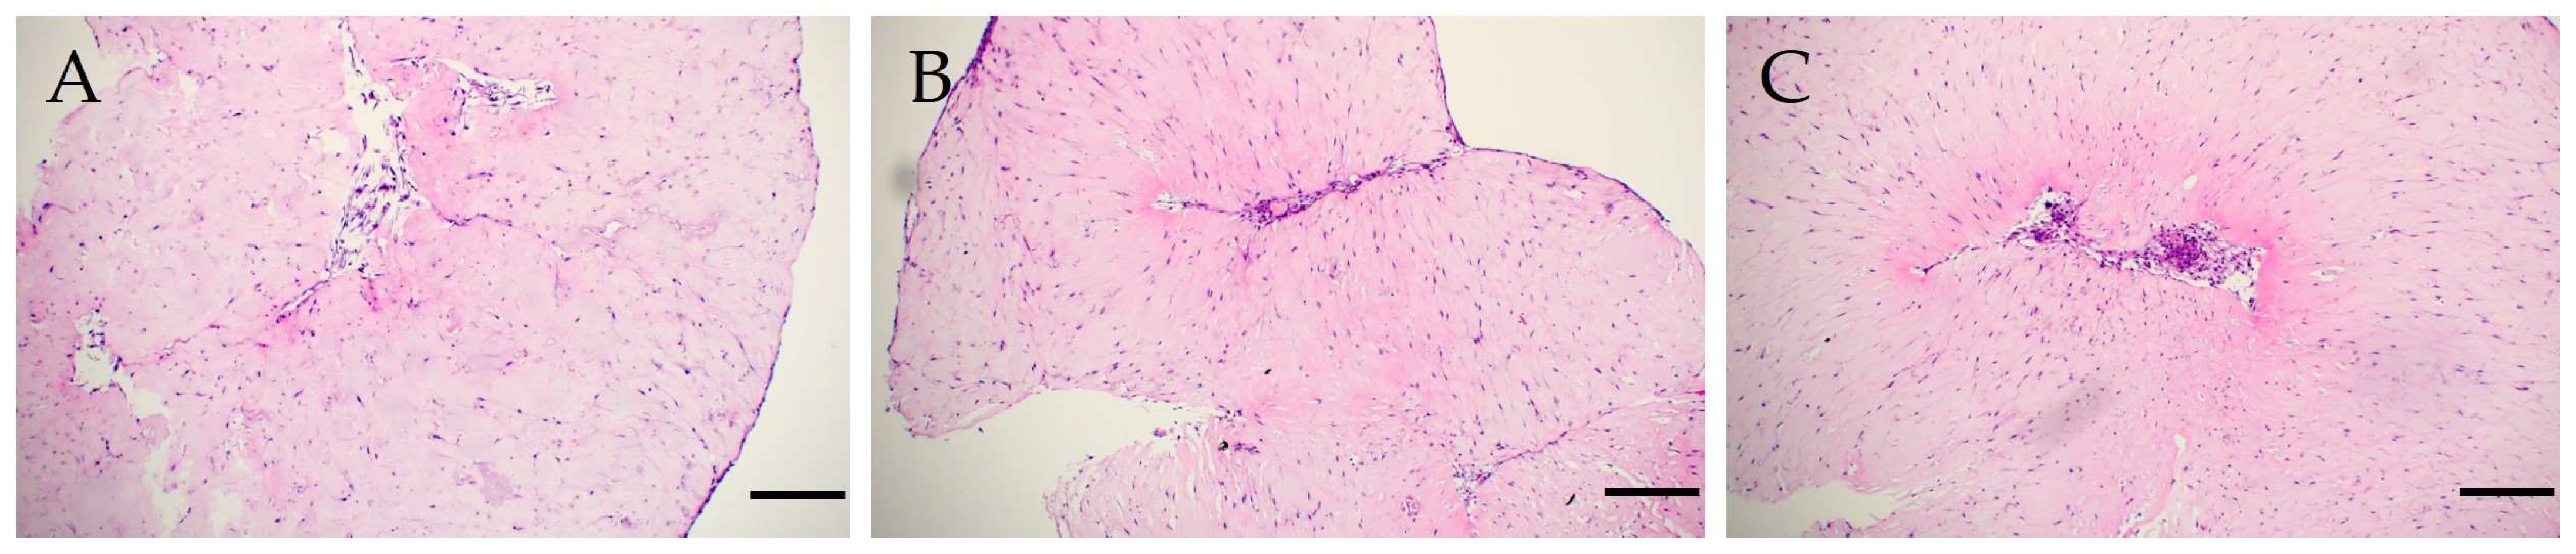

3.1. Morphological Characteristics